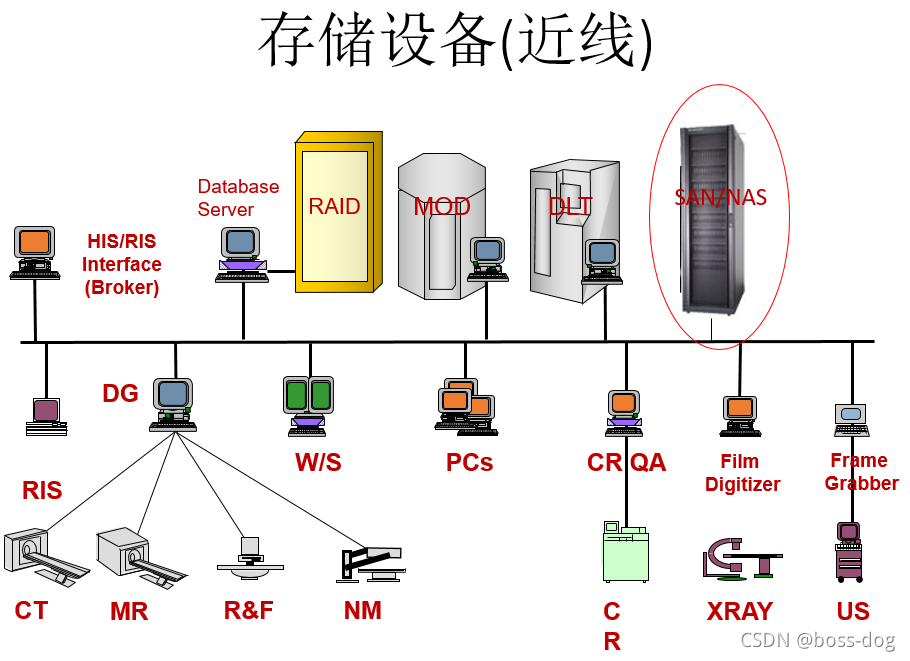

- PACS系统的组成:

HIS/ RIS(关于病人的信息、预约信息)

Broker(代理)

ePR gateway(网关)

Database Server(数据库)

Image Server (RAID)(图像数据库)

Long Term/ Near line Archive(长期、近期的档案整理)

Networks(网络)

Digitizer(数字化处理)

Acquisition Gateways(采集网关)

Non-DICOM modality gateway(非DICOM格式图像的处理)

DICOM Print Server(需要连接胶片打印机)

Media Server(拷刻成光盘)

Reporting Server(形成意见报告)

Monitor QC Server(和显示器的连接)

Web Server(Web服务端)

Workstations(给医生看图片的工作站)